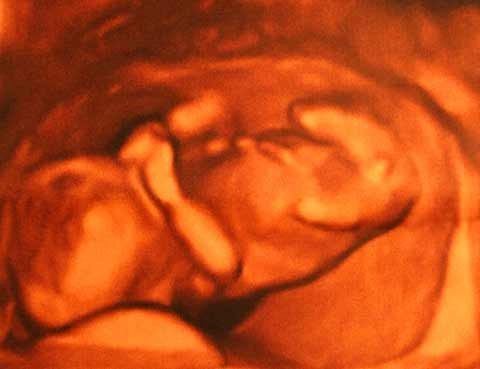

The second set of octuplets ever born in the United States arrived this week, raising questions about the future of baby-making and fertility medicine, a field that has made dramatic advances since the first test-tube baby was born three decades ago.

Fewer multiple births in future One of the breakthroughs in fertility medicine in years to come will be fewer multiple births, Grifo said, and the decline is already under way. "I can't remember the last time we saw more than triplets, and now we have our triplets down to a very low percentage of deliveries," he told LiveScience. About a quarter of all infertility problems in women are related to ovulation problems, so one of the most common treatment approaches is medicines such as Clomid (clomiphene citrate) which can induce the ovulation of follicles — clumps of cells that include the egg or ovum. The challenge is controlling the number of follicles induced, which can lead to multiple births, but proper dosing can help, Grifo said. Clomid is relatively inexpensive compared to other fertility treatments, such as in-vitro fertilization (IVF or "test tube babies"), so for that reason and others, the typical sequence that many patients with fertility problems go through is to start treatment with Clomid. If that fails, the sequence tends to be to then try an injectible ovulation inducer, then IVF if the injections fail, and then an egg donor, with corrective surgery as a possibility along the way for some patients. Clomid treatment, in Grifo's practice and research, results in a doubling of the natural pregnancy rate, he said. The twin percent rate is naturally 2 percent and goes up to 8 percent with Clomid treatment, and the triplet rate with Clomid is 1 in 1,000, "so for us we found it very useful," he said. "Our experience with injectibles is a 10 to 20 percent pregnancy rate per cycle. You can do it safely; you just have to be more careful," Grifo said. Advances with 'test-tube babies' The most effective treatment for infertility is IVF, Grifo said, giving the following success rates (delivery): * for those under 35 years old, more than 50 percent; * up to age 38, 34 percent; * age 40, 29 percent; * age 43, 15 percent, * age 44, 6 percent. Grifo's team also is involved in "blastocyst culturing" prior to IVF, which involves culturing embryos for up to five days and then implanting only the best one or more embryos. "We're at the point where we are doing single embryo transfers," Grifo said, adding that his team will soon publish research describing this process and its successes — very high pregnancy rates in a select group of patients, resulting in no triplets and very few twins. Questions about Clomid A study last year in the journal BMJ Online found that medical interventions for infertility did not improve fertility. The researchers compared the effectiveness of oral clomiphene citrate, intrauterine insemination (IUI, also known as artificial insemination, involves injecting sperm into the uterus) and just trying for a natural pregnancy with no medical assistance. The subjects were women who had experienced unexplained fertility for more than two years. Women who had no interventions had a live birth rate of 17 percent, while the clomifene citrate group had a birth rate of 14 percent and the group having IUI had a birth rate of 23 percent. Grifo called that an "awful study" and said he could not believe it was published. The treatment group excluded patients who responded optimally to clomiphene citrate to avoid multiple births, he said, so the group only included poorly responding patients who already had a low pregnancy rate.

Advances in genetics are opening the door to such baby-making approaches as reprogenetics, which could theoretically make it possible for parents to control the genetic make-up of their children before they are born, via screening or even engineering of genes.